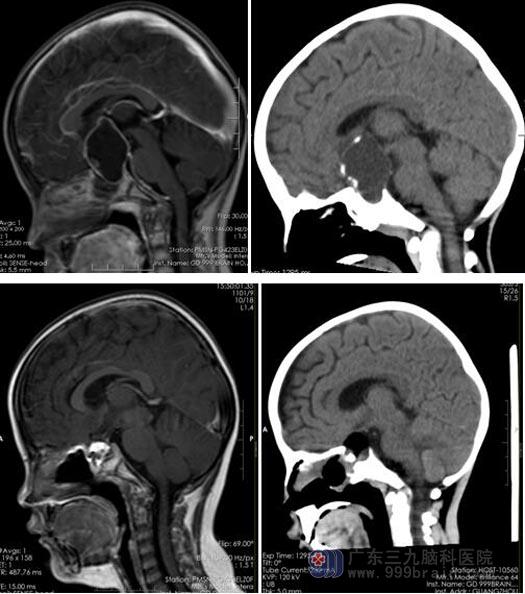

住院后第四天,经过神经外科、肿瘤科、内分泌科、放射科的联合会诊,一致认为患者为小儿颅咽管瘤,并起源于垂体柄中央 ,孩子已经出现垂体功能损害,皮质醇下降,待补充后再行手术治疗,术后需根据内分泌结果考虑是否需要替代治疗,必要时要行放射治疗。鲁明考虑到肿瘤起源于垂体柄和下丘脑并延伸入鞍内,孩子的激素水平正常后,可以采用对患儿创伤少并肿瘤全切率高的内镜经鼻蝶入路切除肿瘤。

由于之前妻子的手术非常成功,马大哥坚持要求鲁明亲自为女儿手术。术中采用神经内镜经鼻入路,在神经导航的引导下,沿着视交叉和垂体的间隙切除肿瘤,术中先释放肿瘤的囊液减压,并直视肿瘤,见肿瘤起源于垂体柄中央,并贯穿垂体柄,上至下丘脑、三脑室底,下至鞍内,沿着肿瘤包膜和蛛网膜的间隙分离肿瘤,充分保护视神经免受损伤,锐性分离肿瘤和双侧下丘脑的黏连部位,术中保留部分垂体柄,切除鞍内肿瘤后垂体保留完整,将肿瘤全切。